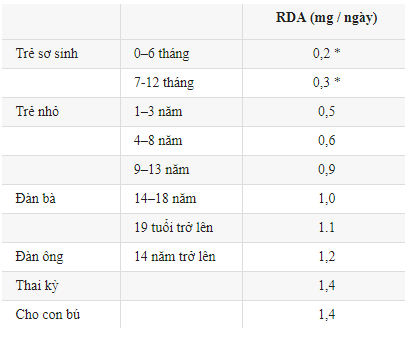

RDA chưa khuyến nghị cho trẻ sơ sinh, Thay vào đó, bảng hiển thị lượng tiêu thụ phù hợp, được đánh dấu bằng dấu (*) là uống đầy đủ.

Những giá trị trên đại diện cho lượng hàng ngày đủ để đáp ứng yêu cầu của hầu hết mọi người.